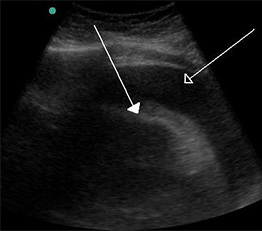

Diagnostic Studies. Pericardial effusions can be diagnosed by medical imaging. Although plain radiography of the chest may suggest the diagnosis, echocardiography is the most expeditious modality to make a definitive diagnosis.26 Both transthoracic (TTE) or transesophageal echocardiogram (TEE) can estimate the size of the effusion as well as its distribution and location, should a pericardiocentesis be required. (See Figure 2.)

Figure 2. Hemorrhagic Pericardial Effusion |

A large hemorrhagic pericardial effusion due to malignancy seen on ultrasound. Source: Doc James. https://commons.wikimedia.org/wiki/File:Hemorragic_effusion.jpg |